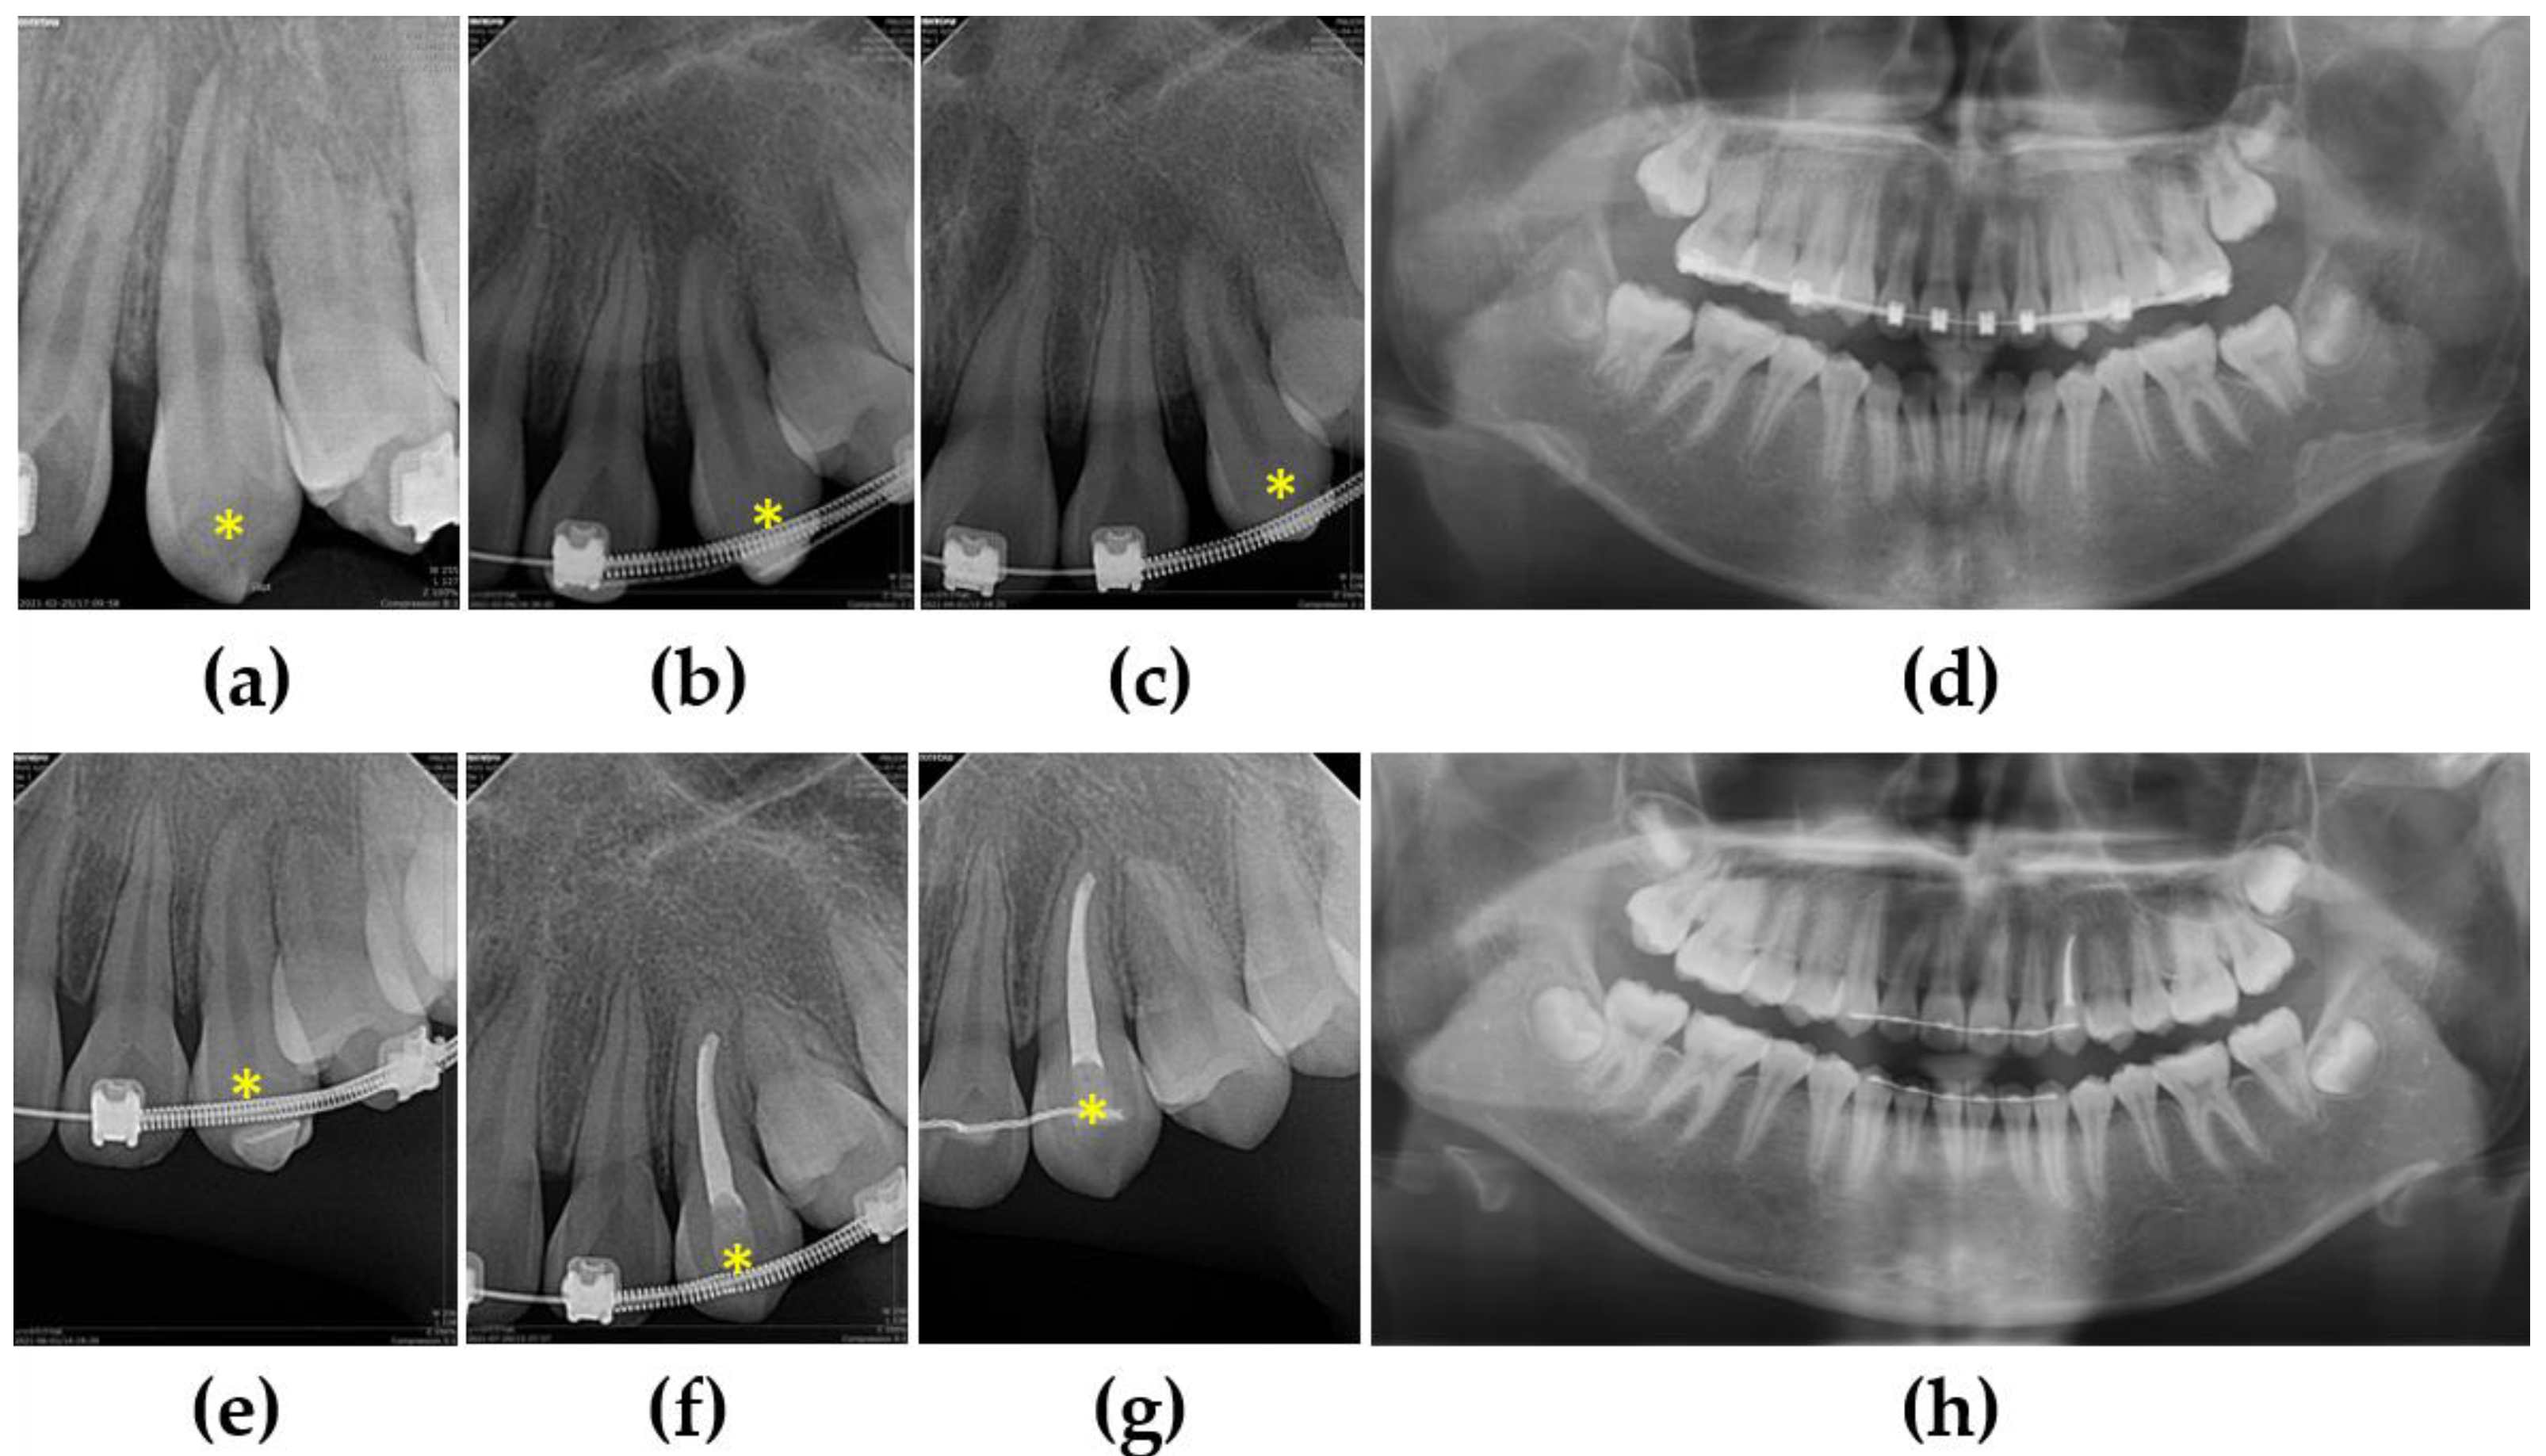

3.1. Case 1